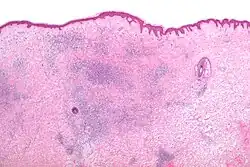

Microscopic appearance

The histomorphologic appearance of insect bites is usually characterized by a wedge-shaped superficial dermal perivascular infiltrate consisting of abundant lymphocytes and scattered eosinophils. This appearance is non-specific, i.e. it may be seen in a number of conditions including:[5]

- Drug reactions,

- Urticarial reactions,

- Prevesicular early stage of bullous pemphigoid, and

- HIV related dermatoses.